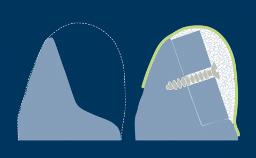

When a tooth is extracted, the alveolar bone that supports the tooth resorbs over time. This resorption results in a reduction in alveolar bone volume, as shown in this clinical example of a missing upper right central incisor. The bone has diminished significantly in orofacial width, and this is in conflict with the fundamental requirement in implant dentistry that implants are placed in the correct prosthodontically determined position. When the alveolar bone resorbs, it is often necessary to augment the bone to ensure that implants can be placed correctly and be completely embedded in bone. This module will describe a specific technique for bone augmentation known as guided bone regeneration or GBR.